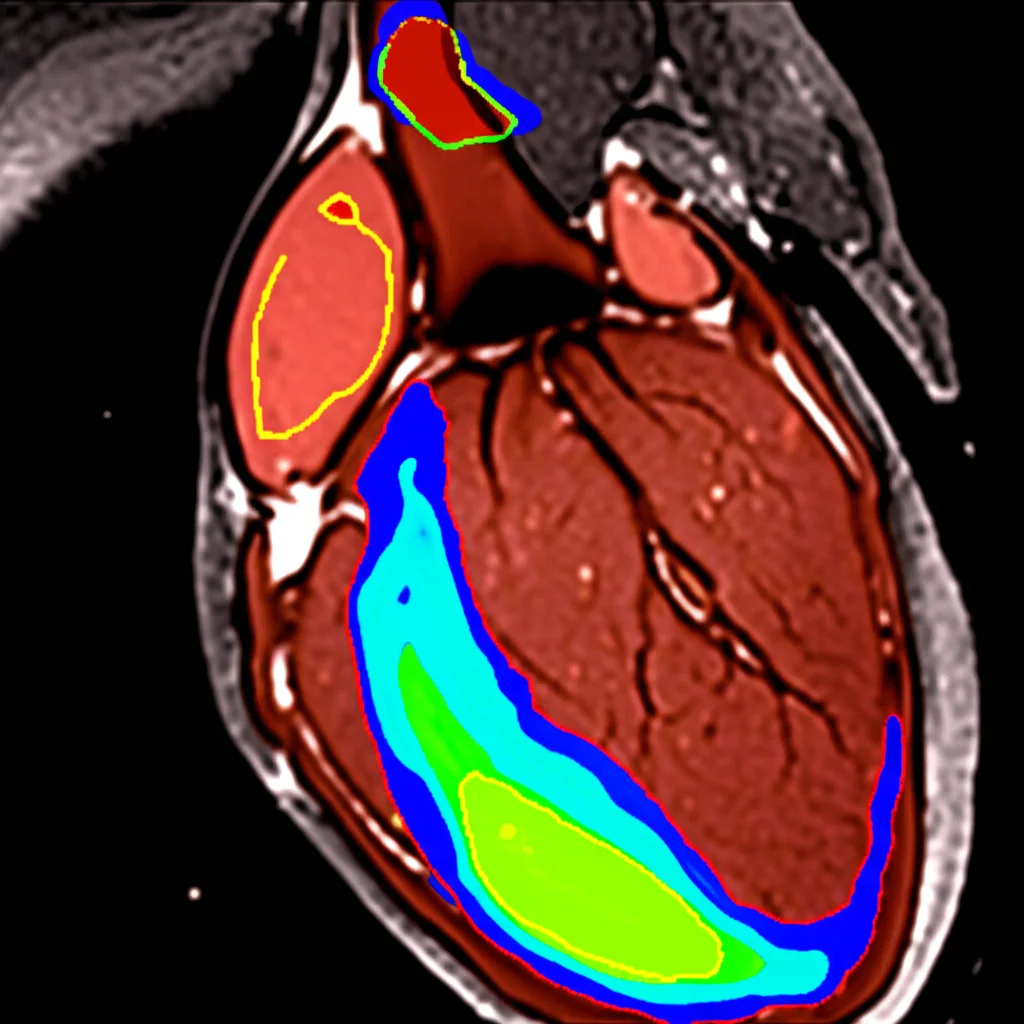

Quando analizziamo queste immagini, non cerchiamo solo l’infarto (MI) in sé. Dobbiamo identificare diverse regioni chiave: la cavità ventricolare sinistra (LV), il miocardio sano (Myo), l’area infartuata (MI) e, a volte, una complicanza chiamata ostruzione microvascolare persistente (MVO). Quest’ultima è particolarmente insidiosa perché è associata a una prognosi peggiore e a un maggior rischio di eventi avversi.

La segmentazione si occupa di tracciare i confini delle quattro regioni chiave (LV, Myo, MI, MVO). Per farlo, abbiamo usato un modello di deep learning chiamato ResU-Net, una variante potenziata del famoso U-Net, che si è dimostrato molto efficace.

- Segmentazione: Il nostro ResU-Net ha ottenuto punteggi F1-score elevati: 91.12% per LV, 88.39% per Myo, 80.08% per MI e 68.01% per MVO. È riuscito a delineare bene anche le aree più piccole e difficili.

Un aspetto cruciale quando si parla di IA in medicina è la fiducia. I medici devono poter capire *perché* un algoritmo prende una certa decisione. Per questo, abbiamo integrato tecniche di Explainable AI (XAI), come le mappe di calore Grad-CAM. Queste mappe evidenziano visivamente quali parti dell’immagine MRI sono state più influenti per la decisione del modello. È come poter sbirciare “nella mente” dell’IA e vedere su cosa si è concentrata per fare la diagnosi. Questo non solo aumenta la fiducia, ma aiuta anche a identificare potenziali errori o bias.